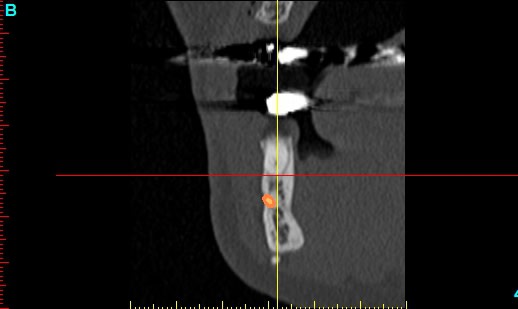

Patiente 58 ans à eu une chirurgie à visée esthétique et "fonctionnelle" adressée pour détartrage en urgence...je ne suis pas spécialiste mais je trouve que la greffe mentonnière est très bof

lésion apicale sur 42 risque de contamination sur la vis en regard..

j'ai demandé un scan en urgence.

Nous sommes d'accord pour la chirurgie mais secteur 4 il y a 2mm être là plastie et la mdble, ça ne me fais pas rêver

La chirurgie à 6 mois

Nous sommes d'accord pour la genioplastie je me suis mal exprimé ce qui m'inquiète c'est la proximité de la greffe, pardon genioplastie et de l'infection de 42, d'une part et la mauvaise liaison de la genioplastie secteur 4, mais je suis peut-être pessimiste.

N'ayant aucune donnée j'essaie d'abord de faire le tri,avant de mettre les mains dedans...je raisonne comme en implanto, quand il y a un foyer infectieux à distance proche (42) je pense qu'il y a un risque...

Plusieurs points: les vis de 15mm x 2mm qui transfixent c'est pas top, une seule plaque, qui plus est non réglable de chaque côté, c'est encore moins top. C'est une plaque de fracture.

En mandibulaire gauche c'est quoi ce fil d'osteosynthese? Un troisième fragment? En laissant l'apex de la 48 pile sur le trait d'osteotomie, je dis chapeau.

Pour la lésion de 42, ca peut être lié à la genio. Forage hasardeux? Mais je vote plus pour une lésion endo/paro

pas simple me semble t il, mais un gros avantage... la sensibilité fait partie du passé, donc je peux "planter" profond....